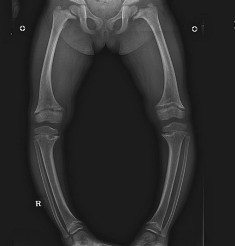

With the advent of newer surgical techniques it is now possible to lengthen a person using Ilizarov or monolateral fixators. Patients who are dwarfs can be treated during their growth phase as they require lengthening in two stages. Children with constitutional short stature are usually lengthened after the completion of growth. The tibial bone is usually lengthened. The reason is that it is easy to lengthen than femoral bone and cosmesis is also better. On an average one bone can be lengthened 6-8 cm in one sitting. The bone is cut and lengthened at a rate of 1mm per day. Using gradual lengthening the muscles, nerves and vessels also lengthen. The results of this method are time tested and proven. However complications like pin tract infection, contracture of tendoachillis and problems of bone regenerate are possible and hence regular follow-up is required.